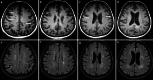

The recently developed effective treatment of primary progressive multiple sclerosis (PPMS) requires the accurate diagnosis of patients with this type of disease. Currently, the diagnosis of PPMS is based on the 2017 McDonald criteria, although the contribution of magnetic resonance imaging (MRI) to this process is fundamental. PPMS, one of the clinical types of MS, represents 10%-15% of all MS patients. Compared to relapsing-remitting MS (RRMS), PPMS differs in terms of pathology, clinical presentation and MRI features. Regarding conventional MRI, focal lesions on T2-weighted images and acute inflammatory lesions with contrast enhancement are less common in PPMS than in RRMS. On the other hand, MRI features of chronic inflammation, such as slowly evolving/expanding lesions (SELs) and leptomeningeal enhancement (LME), and brain and spinal cord atrophy are more common MRI characteristics in PPMS than RRMS. Nonconventional MRI also shows differences in subtle white and grey matter damage between PPMS and other clinical types of disease. In this review, we present separate diagnostic criteria, conventional and nonconventional MRI specificity for PPMS, which may support and simplify the diagnosis of this type of MS in daily clinical practice.